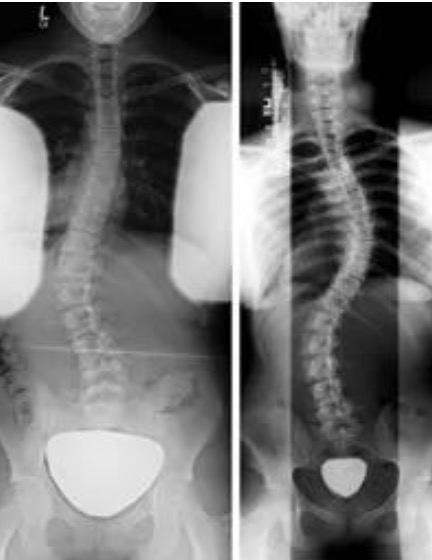

脊柱侧弯术后要注意的问题以及的康复重点

术后康复训练要点:1、肺部功能训练:正确的咳嗽、咳痰;吹气球;向没有装满水的瓶子里吹气。2、胃肠功能训练:患者术后1-3天会出现腹胀,这是正常的,建议以流质饮食为主,粥或蛋白粉等,可以按摩腹部,也可以做自主收复提肛的运动,促进肠道提起排出 3、四肢功能训练。.....